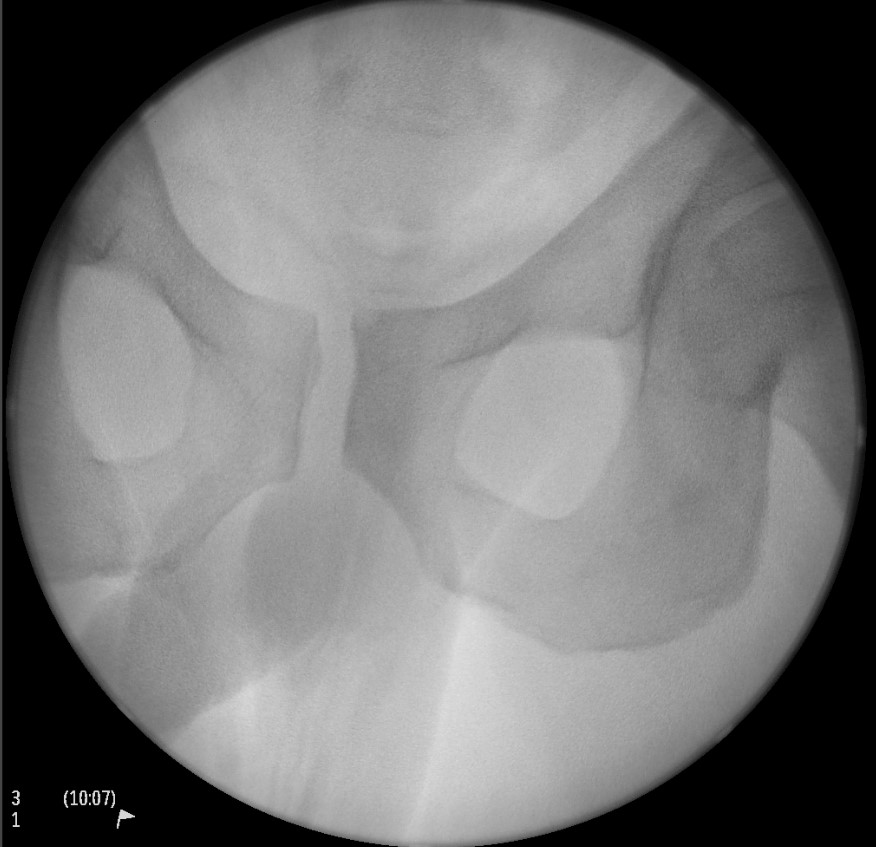

Radiolucent table with image intensifier

- 45o cephalad and caudal / inlet and outlet views

Guide wire insertion into body of S1

- anatomic safe zone

- between S1 foramen and superior ala on outlet view (outlet view)

- between neural canal and anterior body (inlet view)